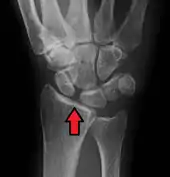

X-ray images indicate scapholunate ligament instability when the scapholunate distance is more than 3 mm, which is called scapholunate dissociation.[7] A static scapholunate instability is generally readily visible, but a dynamic scapholunate instability can only be seen radiographically in certain wrist positions or under certain loading conditions, such as when clenching the wrist, or loading the wrist in ulnar deviation.[6]

In order to diagnose a SLAC wrist you need a posterior anterior (PA) view X-ray, a lateral view X-ray and a fist view X-ray.[8] The fist X-ray is often made if there is no convincing Terry Thomas sign. A fist X-ray of a scapholunate ligament rupture will show a descending capitate bone. Making a fist will give pressure at the capitate, which will descend if there is a rupture in the scapholunate ligament.

Dynamic scapholunate instability visible upon clenching the wrist